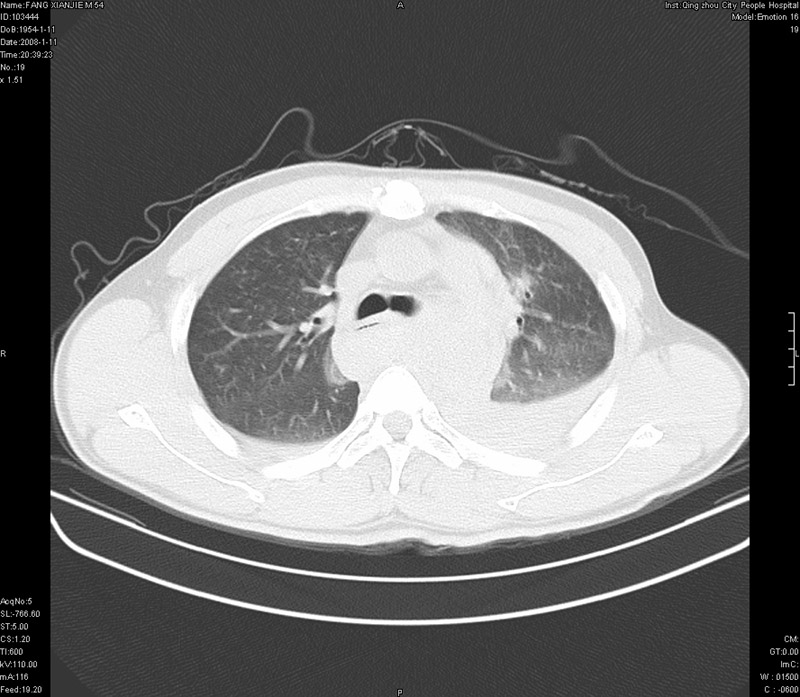

男性,40岁。胸部被车压伤伴胸痛1小时来院就诊。检查:一般情况尚可,血压110/80,胸部及上腹部压痛。结果在三天后公布。骨窗在横断位、冠矢状显示肋骨、胸椎、和胸骨未见骨折征象。

ct11308:胸部外伤1小时(证实病例) (2008-1-13 16:2)结果如下:病人入院后两小时后症状加重,8小时后在征得病人家属同意做了ct增强扫描。如下图。最终临床诊断:外伤性胸主动脉破裂并纵隔内血肿。由于有运动性伪影,胸骨在矢状面重建的图像似有骨折征,这是一种假象,我们称之为“假骨折”,这在多层ct重建中经常性遇到,必要时要结合横断图像鉴别之。现在,病人的一般情况较差,是否要手术家属尚有争议,如果手术修补,难度较大,需要专门预定制作固定支架。

当然,对于该病例,其它非重要的诊断还有:右侧少量气胸;左侧胸腔积液;左侧轻度肺挫裂伤。对于纵隔内血肿,我们曾经遇到过多例,也有怀疑主动脉的破裂,但是,均未得到具体出血部位的明确诊断。